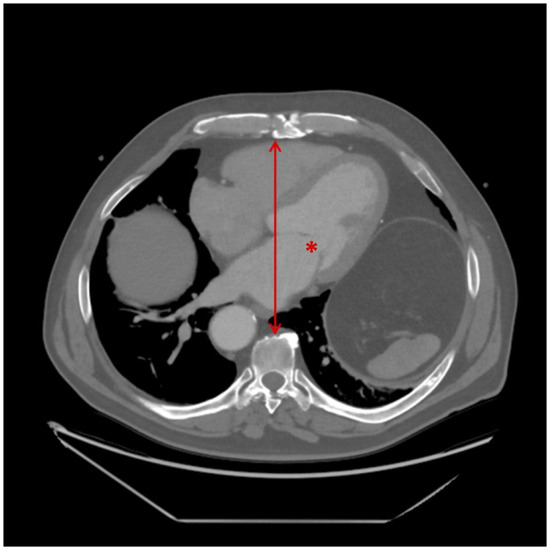

Complex surgical procedures were defined as complex valve repair or combined surgeries, such as double valve procedures. Anteroposterior (AP) diameter/distance was measured from the posterior table of the sternum to the anterior aspect of the vertebral body at the level of the mitral valve on CT scans (Figure 1). Renal failure was defined using the Kidney Disease: Improving Global Outcomes (KDIGO) criteria, as follows: (i) an increase in serum creatinine by ≥26.5 µmol/L within 48 h, (ii) an increase to ≥1.5 times baseline within 7 days, or (iii) urine output <0.5 mL/kg/h for 6 h.

Figure 1. Measurement of anteroposterior (AP) diameter on preoperative CT imaging. The asterisk (*) indicates the mitral valve at the approximate level of A2/P2. The line with arrowheads represents the anteroposterior distance, measured from the posterior aspect of the sternum to the anterior surface of the corresponding vertebral body.